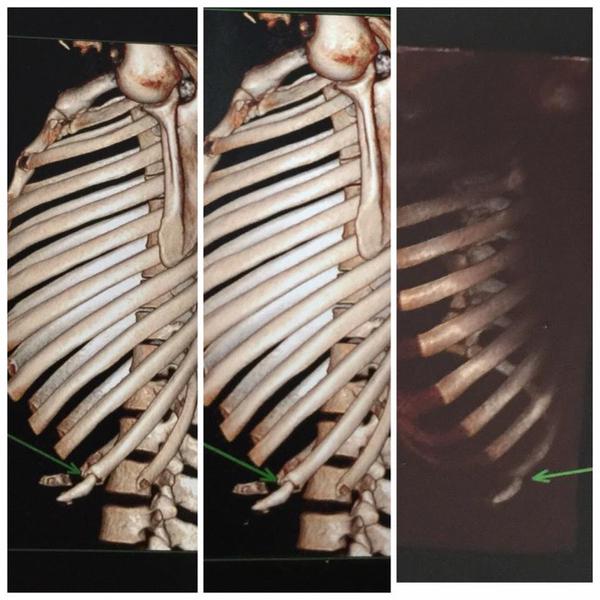

It seems that the MMA community has received closure after weeks of gossip, rumors, and smack talk from Conor McGregor and his sugar-daddy/promoter Dana White; Joe Aldo’s rib is most definitely broken. Specifically, his 10th rib on his left side.

Jose Aldo broke rib 10 on his left side which is in a real problem area. Bas Rutten illustrated this on ESPN’s Sports Science with a vicious hook targeting the same area.

The placement of Rib 10 along the rib cage itself is also problematic.

Rib 10 has no such protection; it is the last rib to attach to the sternum and the two ribs below it do not come out far enough. This means that a strike that travels at an upwards trajectory (like Rutten’s shovel hook) can hit Rib 10 with no other rib to cushion the force.